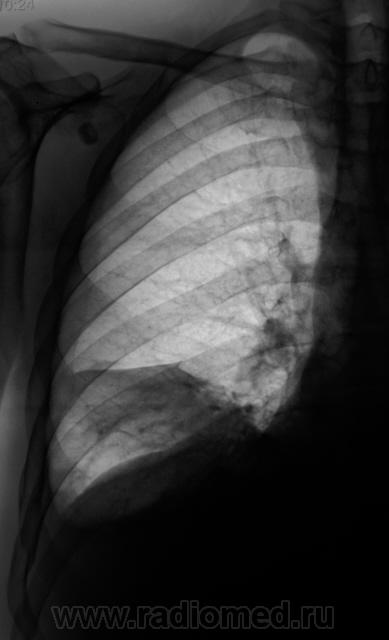

Пациент направлен на исследование с диагнозом "Правостороняя пневмония".

Междолевое осумкование выпота справа. Ну и конечно двустор.свободный.

Явная приподнятость диафрагмы настораживает...

Поскольку такой внезапный парез диафрагмы маловероятен...смею предположить наличие базального плеврита справа...он же - диафрагмальный плеврит. Здорово бы было посмотреть на УЗИ - за три секунды решили бы проблему.